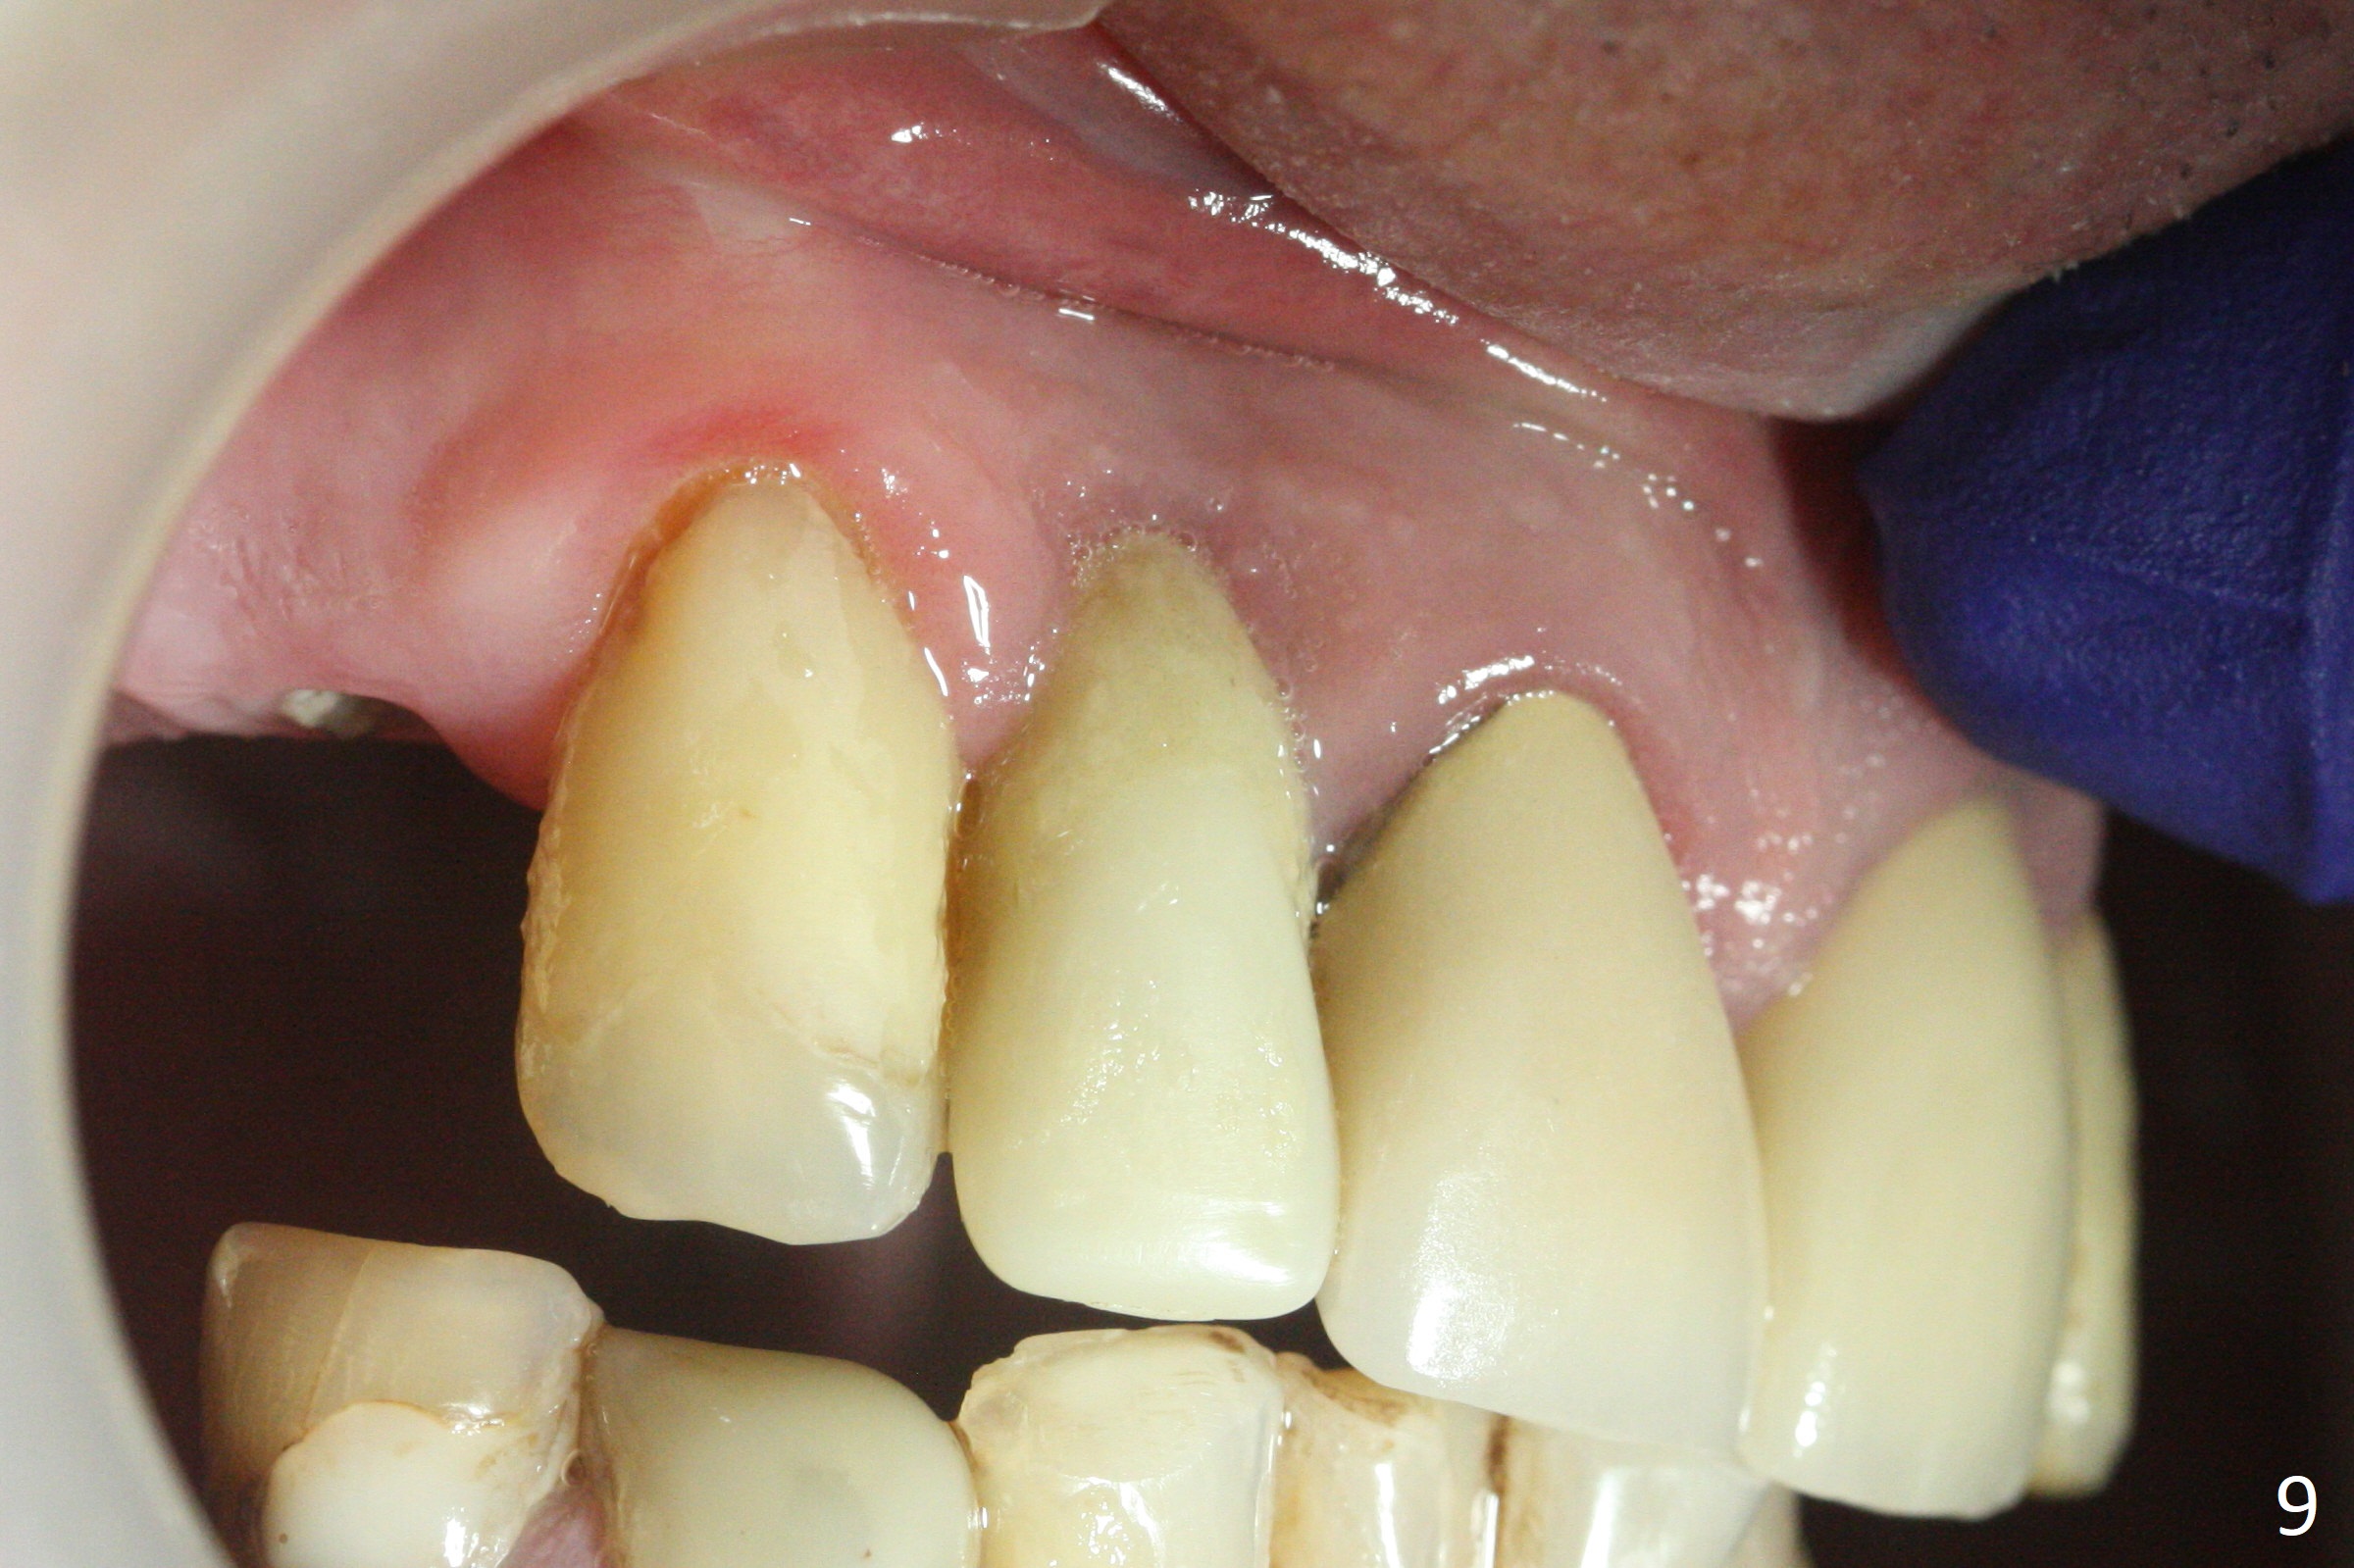

The residual root at #7 is fairly well exposed with buccal gingival recession (Fig.1). The implant placement is flapless (Fig.2-7). What is not shown is that the 3.8x13 mm implant is buccally subcrestally placed (Fig.3). After 1st round of bone graft buccal to the implant, a 4.5x5(5) mm abutment is immediately placed and prepared (Fig.4,5). An immediate provisional is placed after 2nd round of bone graft subgingivally buccally (Fig.6,7). Note the bulging gingiva (*), as compared to that in Fig.4,5. The long implant is chosen because of anterior deep bite (Fig.4) and lack of posterior support (Fig.7).

The gingiva adapts well to the provisional 1 week postop (Fig.8). The buccal gingiva remains recessive and the buccal plate is concave 5.5 months postop (Fig.9-11). It appears that the coronal portion of the buccal plate is resorbed 12 months postop (6 months post cementation, Fig.12 >). Socket shield or smaller diameter implant should have been done to avoid bone loss. Reanalysis of CBCT reveals that implantation apparently increases the bone width and that the buccal plate resorption is not so severe (Fig.13,14 (>: coronal end of the buccal plate)). Panoramic X-ray is taken 2 year 5 month post cementation.